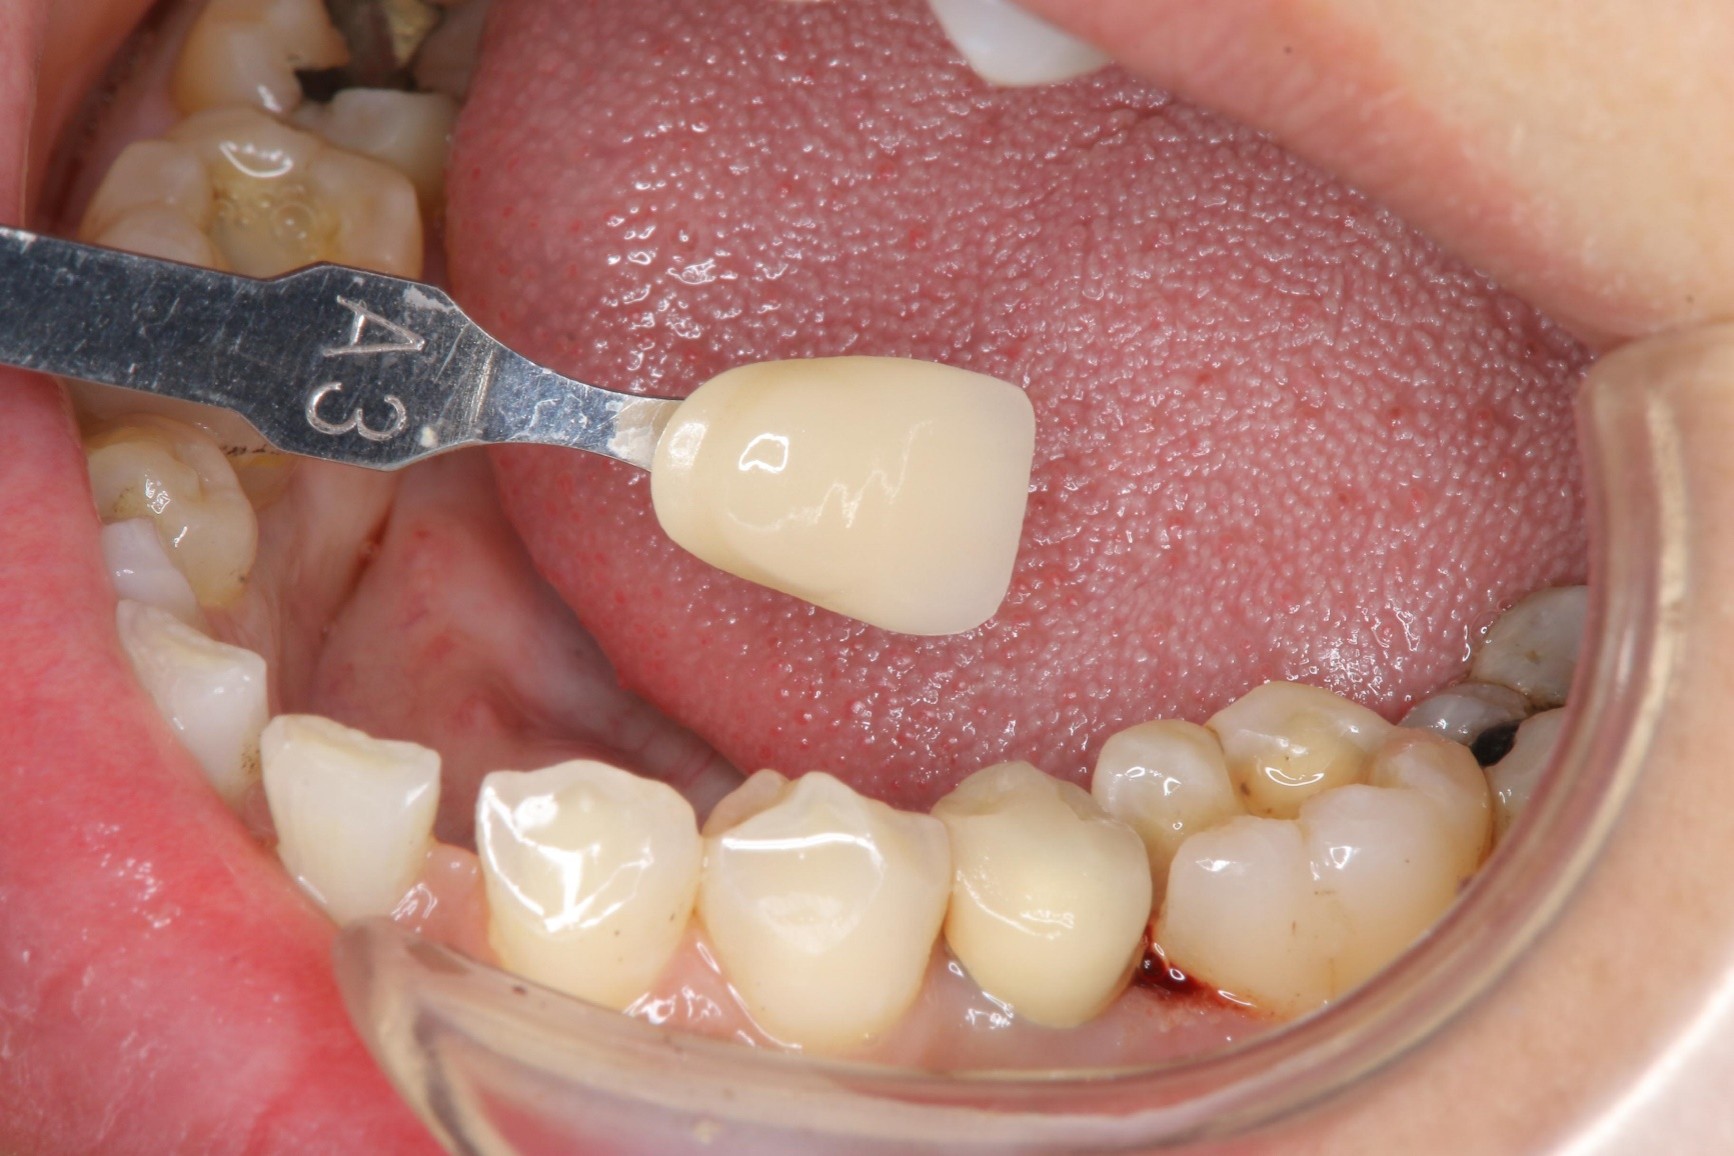

照相比色